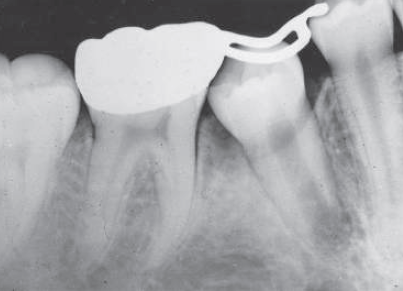

2 / 30

2. (Select ONE OR MORE correct answers)

The radiograph shows evidence of